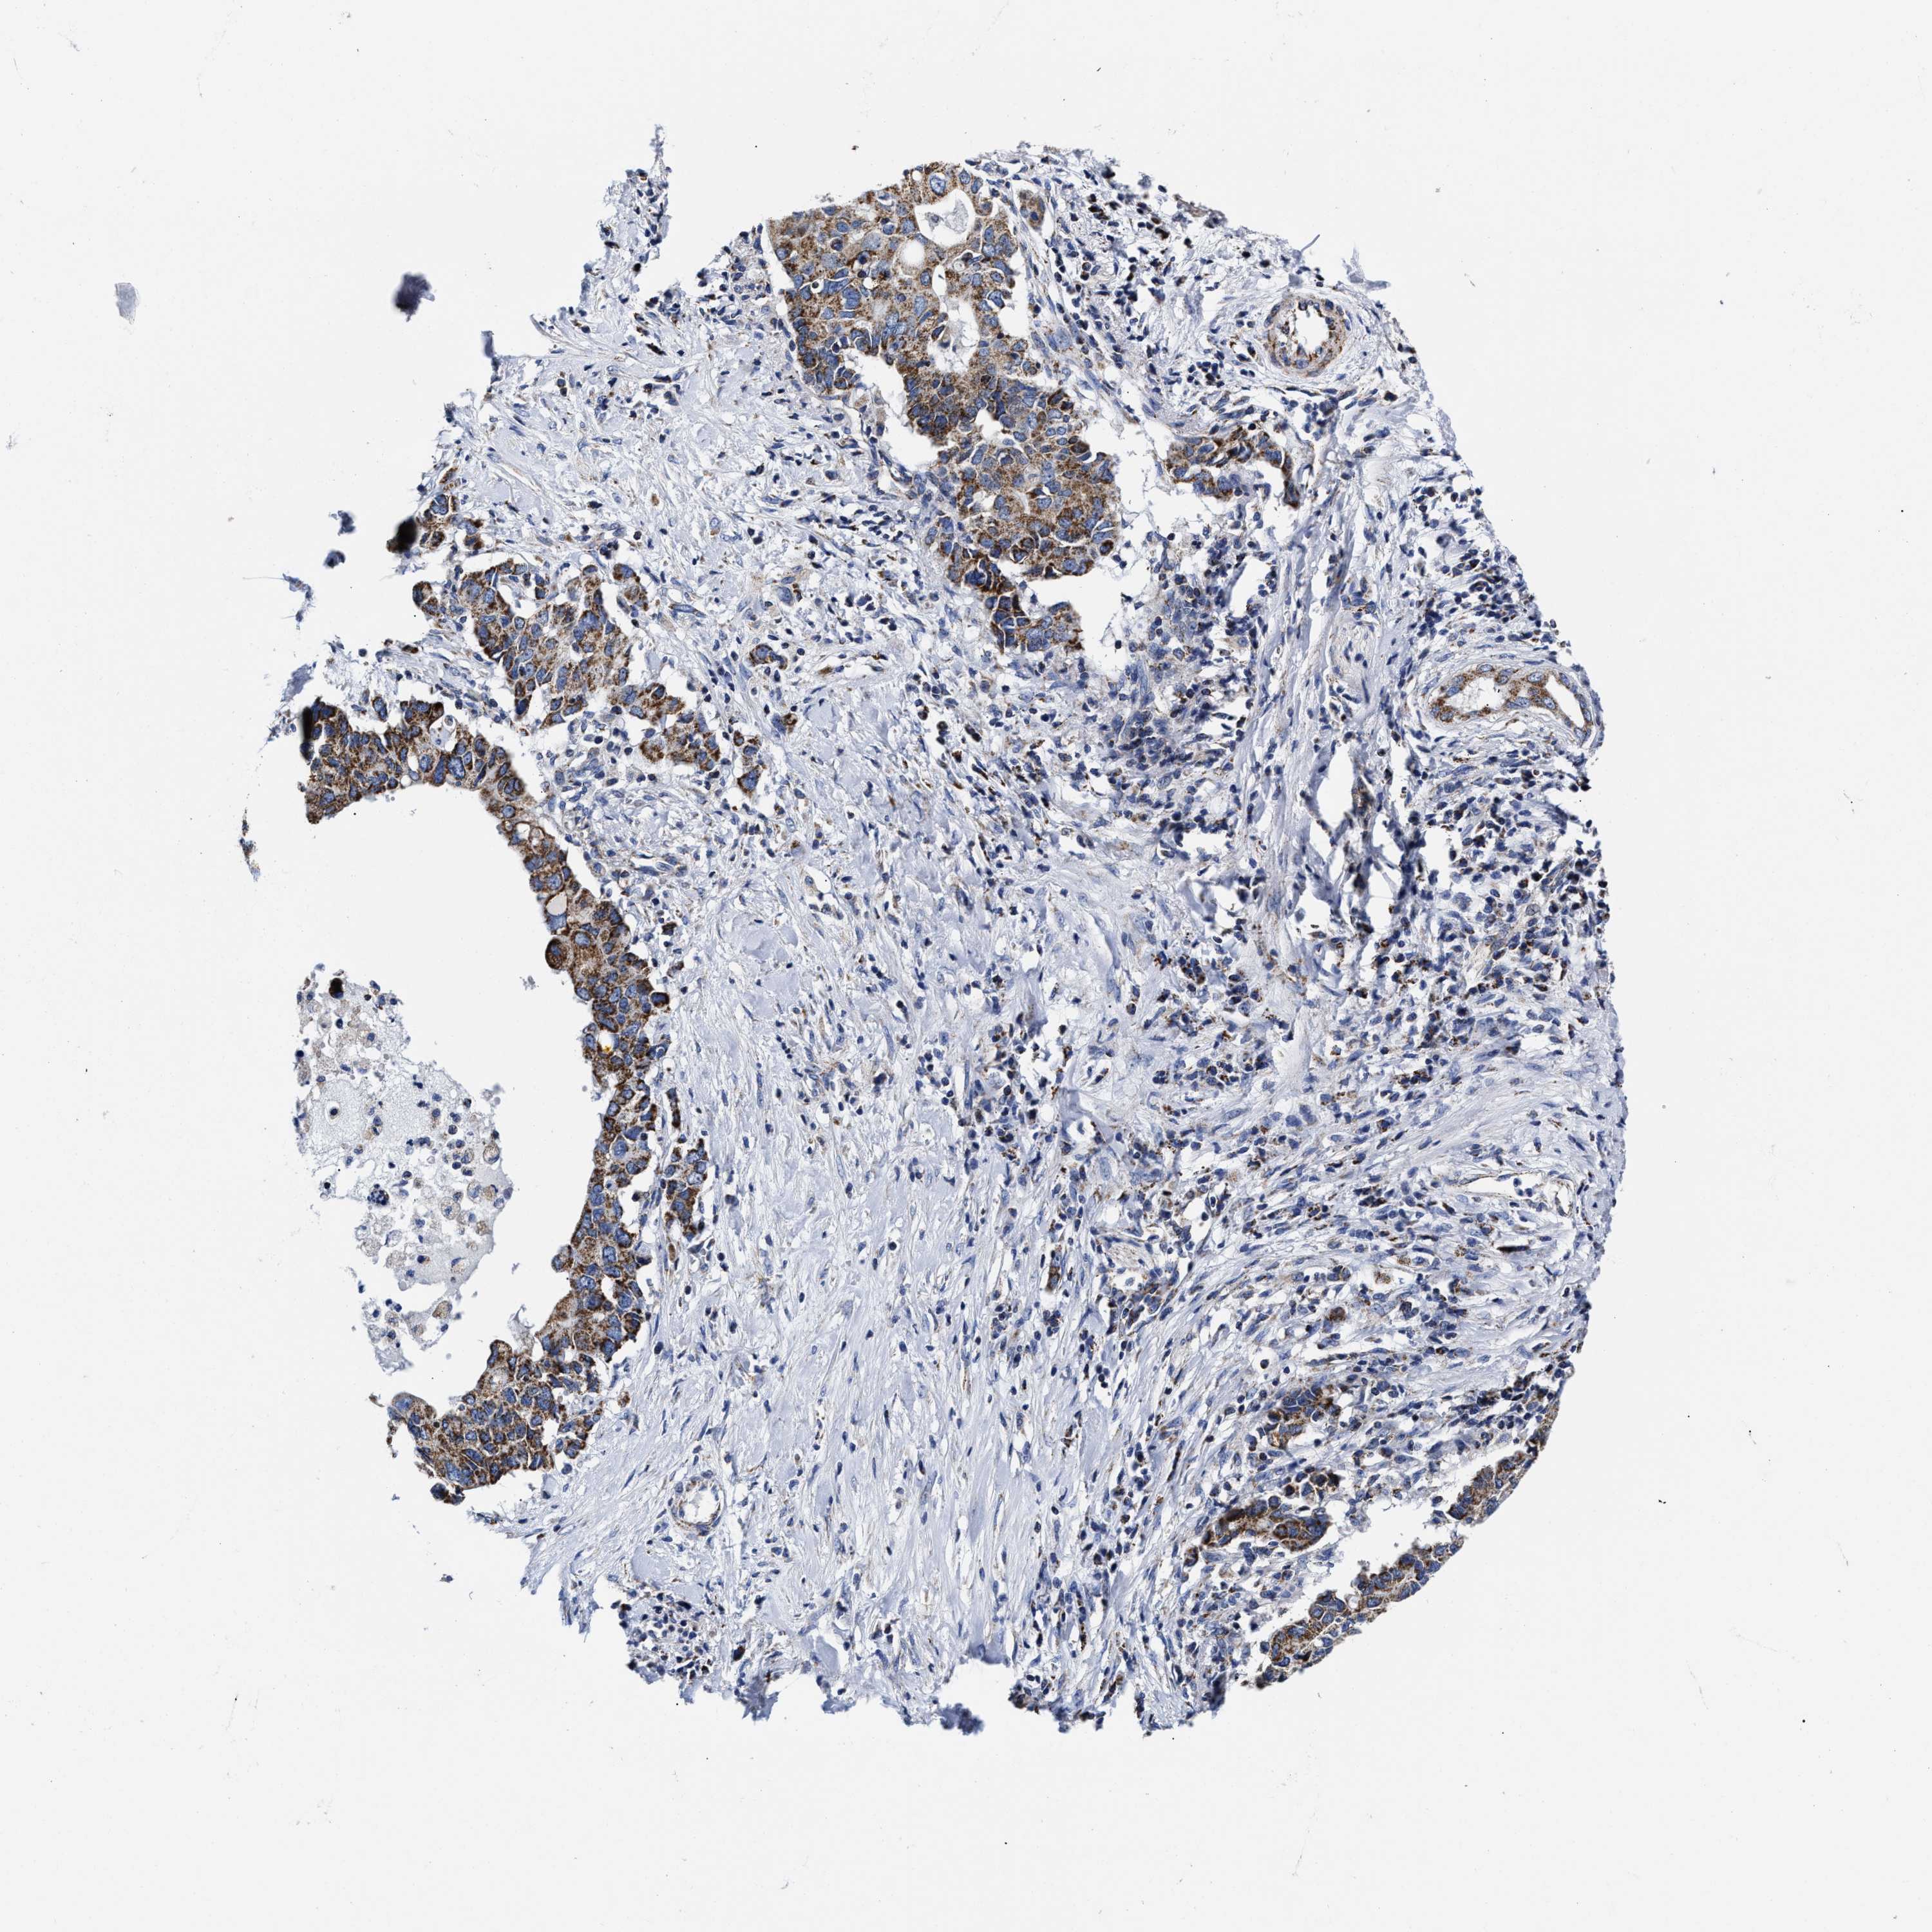

PANCREATIC CANCER - Protein expressioni

A mouse-over function shows sample information and annotation data. Click on an image to view it in a full screen mode. Samples can be filtered based on level of antibody staining by selecting one or several of the following categories: high, medium, low and not detected. The assay and annotation is described here.

Note that samples used for immunohistochemistry by the Human Protein Atlas do not correspond to samples in the TCGA dataset.

Antibody stainingi

Antibody staining in the annotated cell types in the current human tissue is reported as not detected, low, medium, or high, based on conventional immunohistochemistry profiling in selected tissues. This score is based on the combination of the staining intensity and fraction of stained cells.

Each image is clickable and will lead to virtual microscopy that enables deeper exploration of all samples and also displays staining intensity scores, fraction scores and subcellular localization as well as patient and tissue information for each sample.

Antibody HPA020961

Antibody HPA059109

Staining

High

Medium

Low

Not detected

Intensity

Strong

Moderate

Weak

Negative

Quantity

>75%

75%-25%

<25%

None

Location

Nuclear

Cytoplasmic/membranous

Cytoplasmic/membranous,nuclear

Adenocarcinoma, NOS